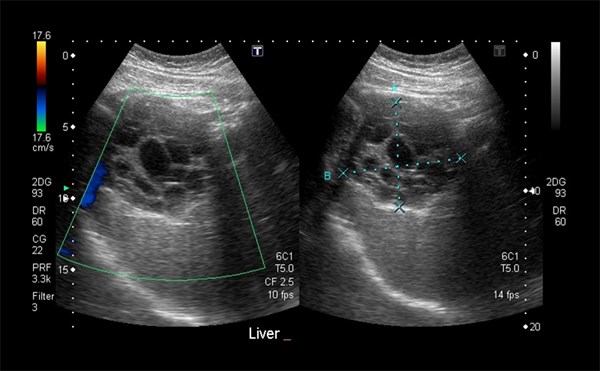

Advanced ultrasound can enhance the diagnosis of organ injury, viable tumor, and vascular pathologies at bedside.